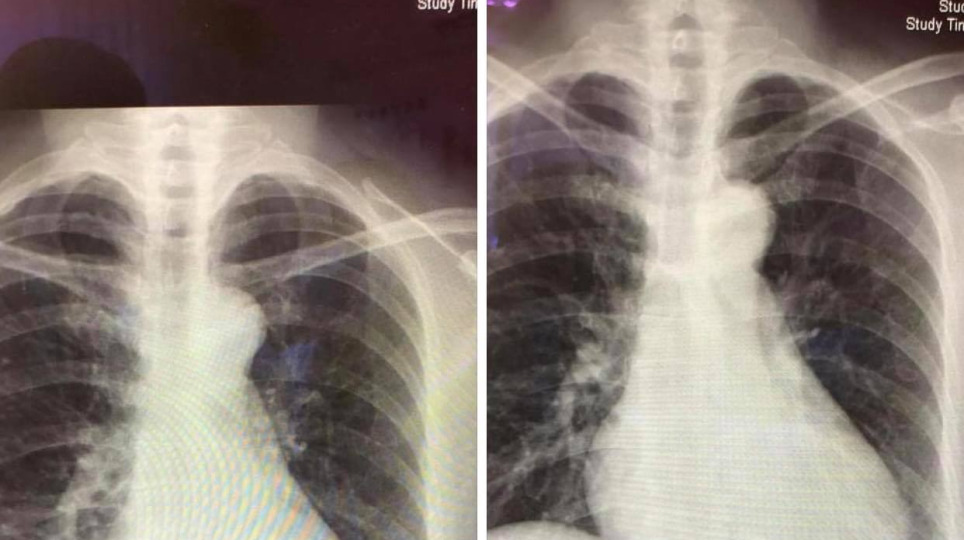

老人健檢出爐主動脈扭曲併鈣化心臟擴大 老人常態?35 快樂日記 2020/10/05(一)